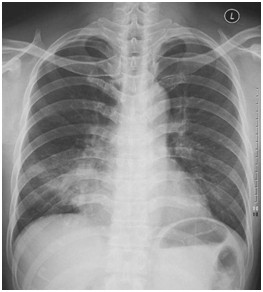

01卷-4.根據(jù)下圖請(qǐng)做出正確診斷(本題滿分2.00分)

A.右肺葉肺炎

B.兩下肺炎

C.右下肺肺癌

D.正常胸片

本題答案:A

【該題針對(duì)“ X線-肺炎 ”知識(shí)點(diǎn)進(jìn)行考核】